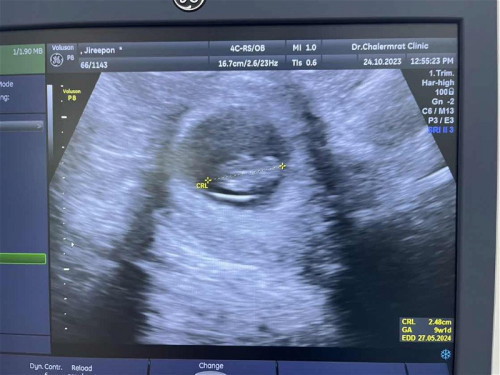

9w ไปอัลตราซาวด์ดูหมอบอกน้องดูนิ่งๆ ปกติแม่ๆอัลตราซาวด์เห็นหัวใจเต้นกันตอนกี่ w ค่ะ ตอนนี้กังวลมาก ท้องแรกค่ะ#ขอบคุณสำหรับคำตอบค่ะ #ท้องแรกคะ #คุณแม่ๆช่วยแนะนำหน่อยค่ะ

มาอัปเดตนะคะ น้องไม่อยู่แล้วค่ะ หัวใจน้องไม่เต้น แม่ยุติการตั้งครรภ์แล้ว โดยการดูดสุญญากาศออกค่ะ #ขอบคุณแม่ๆทุกคนที่แวะมาคอมเม้นและให้กำลังใจนะคะ ❤️